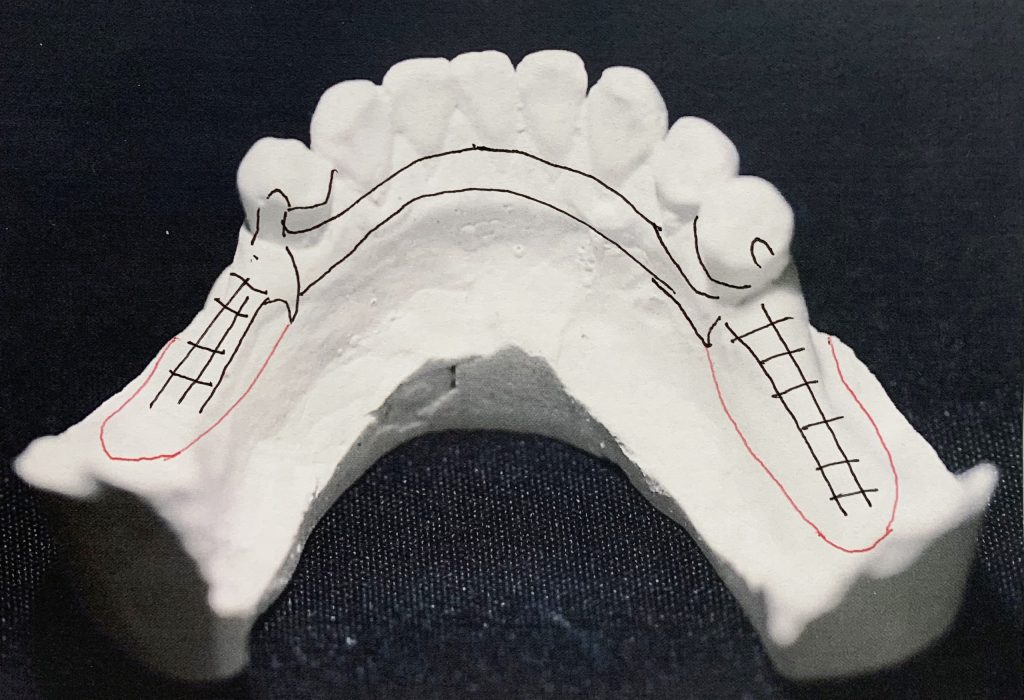

To prevent displacement of partials, away from oral tissue and rotational movements, retention is obtained by direct and indirect retainers. Optimum support of distal extension denture base is necessary as well as the use of flexible direct retention to prevent torquing forces transmitted to the abutment teeth. Additionally, the equitable distribution of occlusal forces preserves the remaining teeth.

Kennedy Class I is a significantly challenging denture since it has a rotational fulcrum: Two flexible direct retention retainers are needed with the use of stress relief clasps that prevent torquing forces to the abutment.

Provision of indirect retention prevents the rotation of the denture.

TCS Flexible Partial – For this particular case prescribing a TCS Flexible Partial is an option because the clasp design will provide the stability required to function properly. However, the TCS/Metal Combo may be a better alternative due to the lack of support in both saddle areas.

TCS/Metal Combo Partial – For a TCS/Metal Combo the Doctor would need to make occlusal preparation in the premolars to avoid interference with the occlusion. The TCS/Metal Combo may be the better option as it will hold up longer and the TCS clasps will provide a better aesthetic option.

Design & Blockout Example

Watch an example of how to design and block out a difficult Kennedy Class I case.

Design for a case with long free end saddles.

The angulation of the teeth present a challenge with path of insertion.

Adding too much blockout could work against you in this case.